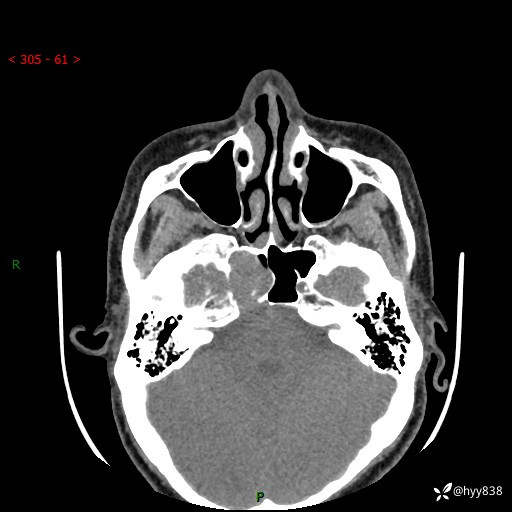

蝶鞍CT平扫